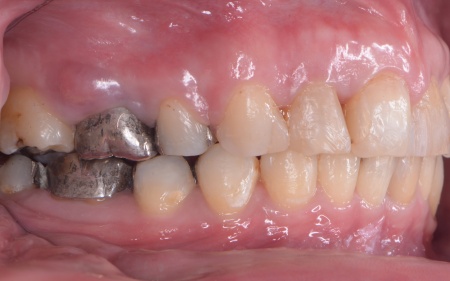

| カウンセリング | 拝見したところ、上前歯が大きく前に出ている上顎前突であり、上下の前歯が噛み合わずに口を閉じても前歯同士が接触しない「開咬(かいこう)」の状態でした。 レントゲン撮影をして詳しく調べた結果、歯の位置だけでなく、骨格的な問題があることが分かりました。 また、前歯で食べ物をうまく噛み切ることができないため、奥歯にも強い負担がかかっているだけでなく、このまま放置すると、奥歯がすり減ったり痛みが生じたりするリスクもあります。 以上のことから、噛み合わせを改善する治療が必要だと診断しました。 |

患者様の場合、骨格的な上顎前突が噛み合わせを乱している主な原因であることから、矯正治療では前歯を後方へ大きく動かすためのスペースを確保する必要があります。 そのため、今回は以下2つの方法を提案しました。 ①抜歯後、アンカースクリューを用いたワイヤー矯正 メリット:骨格的な上顎前突に対応しやすく、前歯を大きく後方へ動かすことができる ②取り外し可能な装置を使用するマウスピース矯正 メリット:装置が透明で目立ちにくく、取り外しができる 以上のメリットとデメリットを丁寧にお伝えしたところ、患者様は①のアンカースクリューを用いたワイヤー矯正を選択されました。 まず、上顎の左右奥歯を抜き、前歯を後方に動かすためのスペースを確保します。 治療の結果、前歯が正しく噛み合うようになり、横顔のバランスも整いました。 矯正治療終了後は、歯が元の場所に戻らないよう上下前歯に保定装置(リテーナー)を装着し、治療を終了しています。 |